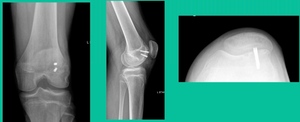

Now a couple of quick cases. This is juvenile OCD. This is the first series of three or four, just juveniles. 14-year-old, intermittent knee pain, lateral femoral condyle OCD (Figure 1).

The challenge is this. This series of patients were populated by early decisions to treat when patients don’t have symptoms. That’s a problem in my mind. Post-Op, they protect their weight-bearing. That’s actually treatment. These are often smaller lesions of the medial femoral condyle. They do really well. That being said, it’s an option. It’s not my option. My option for someone who’s macroscopically unstable is we use biocomposite screws (Figure 4).

These biocomposite screws will hang around for upwards of a year. So, they’re not innocuous, and you’ve got to bury their heads. But we drill it, we tap it, and we stabilize it, and then we drill from the side in an effort to promote further biology. This is analogous to just arthroscopic fixation, but I don’t go back, and I don’t remove the screws. Then I’ll typically take a K-wire from the side after I place these screws. I keep them non-weight-bearing for eight weeks. I don’t remove it. I wait four months before they go back to high-impact activities like this patient did here.

What are the outcomes? Very, very favorable. We had 87% survivorship using a biocomposite screw. Would I use it for a macroscopically unstable one? I wouldn’t. I would tell you that the biomechanics are not nearly as good, and it is not innocuous. If you leave the head proud, this will scratch the tibia and cause a railroad track there. You must bury them, but don’t take them out.